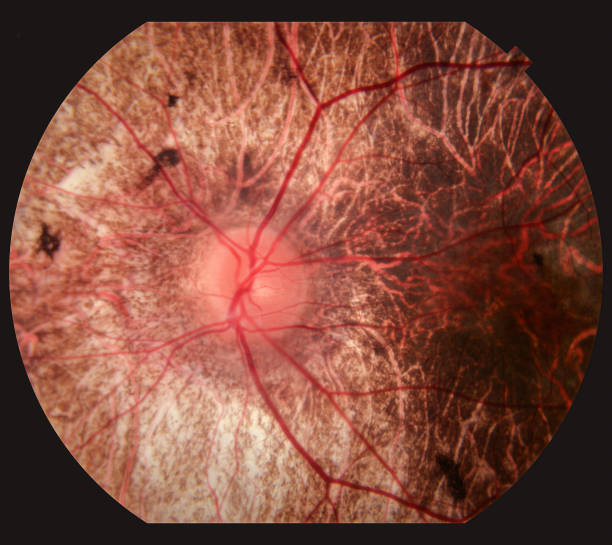

결막염 증상

결막염의 증상은 종류에 따라 다르지만 대부분의 경우 눈물, 충혈된 눈, 점액이 1주일 정도의 잠복기를 거쳐 처음 나타날 수 있습니다. 일반적인 결막염 증상은 다음과 같습니다.

- 눈이 빨갛고 가렵고 눈물이 나는 경우가 많습니다.

- 눈부심 현상이 심해지고 눈이 이물감이 생깁니다.

- 점액이 많아 아침에 눈을 뜨기가 쉽지 않습니다.

- 눈꺼풀이 부어 있습니다.